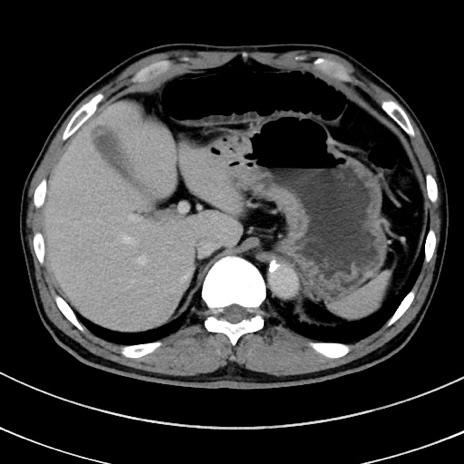

症例8(横断像)

【症例】 60歳代男性

【主訴】 黒色吐物

【現病歴】 4日前から嘔気自覚、2日前の朝食後にも嘔気あり、自分で手で嘔吐反射起こし嘔吐したところ血が混ざっていたため受診。

【既往歴】 5年前汎発性腹膜炎を伴う急性虫垂炎で手術、高血圧、前立腺肥大症、高脂血症

【身体所見】 腹部正中に手術癩痕あり 腹部平坦・軟圧痛なし膨満感あり

【データ】WBC 8400、CRP 4.54